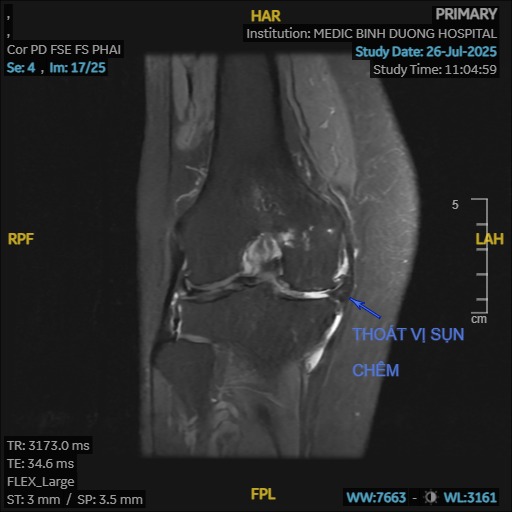

- Chấn thương: Các chấn thương cũ ở khớp gối (gãy xương, rách sụn chêm, tổn thương dây chằng) có thể làm thay đổi cấu trúc khớp và đẩy nhanh quá trình thoái hóa.

- Khớp phát ra tiếng kêu: Khi cử động khớp gối có thể nghe thấy tiếng lục khục, lạo xạo do bề mặt sụn khớp bị gồ ghề.

- Nội soi khớp: Cắt lọc, bào, rửa khớp, khoan kích thích tạo xương (microfracture), cấy ghép tế bào sụn.